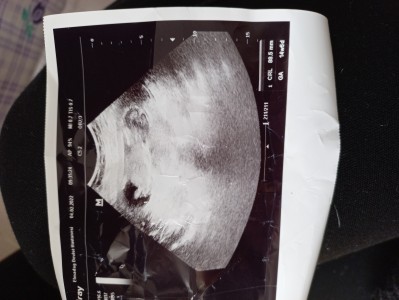

Daha erken ve fotoğrafta pek belli değil ama genede içinizden ne geçiyor bilmek isterim

Gebelik haftası 14+5

Ultrason kağıdı tam net değil ama erkek gibi duruyor sağlıkla doğsun inşallah